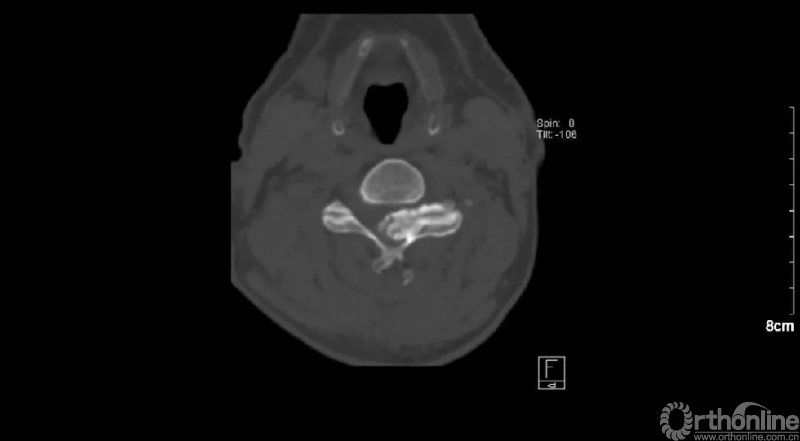

入院查体患者四肢肌张力高,双侧hoffman阳性。CT及MRI检查提示C4/5左侧关节突内缘有一巨大骨块(15mm*16mm),相应节段椎管严重狭窄。椎管内骨块的前端还有一游离骨块。

影像学资料